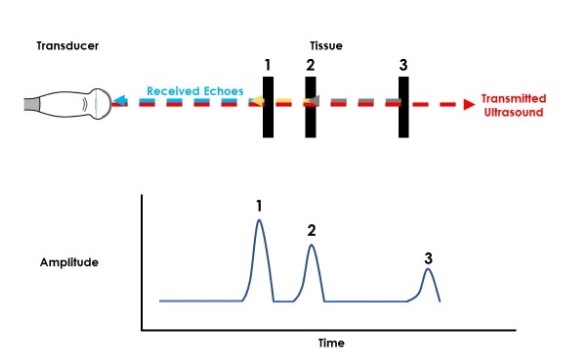

A-Mode (Amplitude Mode)

در این حالت، اطلاعات بازتابی به صورت نمودار یکبعدی نمایش داده میشوند که محور افقی نشاندهنده زمان (یا عمق) و محور عمودی نشاندهنده دامنه بازتاب است. هر قله (peak) در نمودار بیانگر یک سطح بازتابدهنده در بدن میباشد.A-mode سادهترین نوع تصویربرداری اولتراسوند است و بیشتر در دستگاههای قدیمی یا در اندازهگیری ضخامت بافتها و ساختارهای خاص مانند قرنیه چشم کاربرد دارد. از نظر فیزیکی، یک پالس فراصوت به بدن ارسال شده و بازتابهای ناشی از مرزهای بین بافتها به مبدل بازمیگردند. زمان رفت و برگشت سیگنال برای تعیین عمق هر بازتاب استفاده میشود.